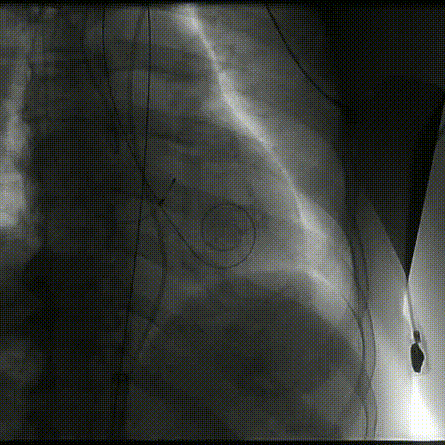

根部造影

定位

第二次释放

释放至可回收极限

术后